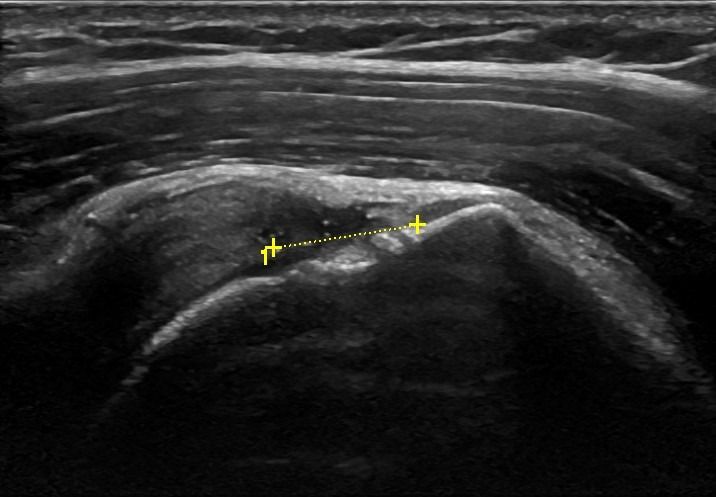

Το Υπερηχογράφημα Ώμου επιτρέπει τον εντοπισμό παθήσεων στους τένοντες του στροφικού πετάλου, όπως:

Επιπλέον, το Υπερηχογράφημα Ώμου μπορεί να διαγνώσει τενοντοπάθεια, τενοντοελυτρίτιδα ή ρήξη στον τένοντα της μακράς κεφαλής δικέφαλου βραχιονίου.

Με το Υπερηχογράφημα Ώμου μπορεί να εντοπιστεί συλλογή υγρού στα εξής σημεία:

Σε περιπτώσεις Ρευματοειδούς Αρθρίτιδας ή Οστεοαρθρίτιδας το υπερηχογράφημα είναι εξαιρετικά σημαντικό για τη διάγνωση υμενίτιδας στην άρθρωση του ώμου.